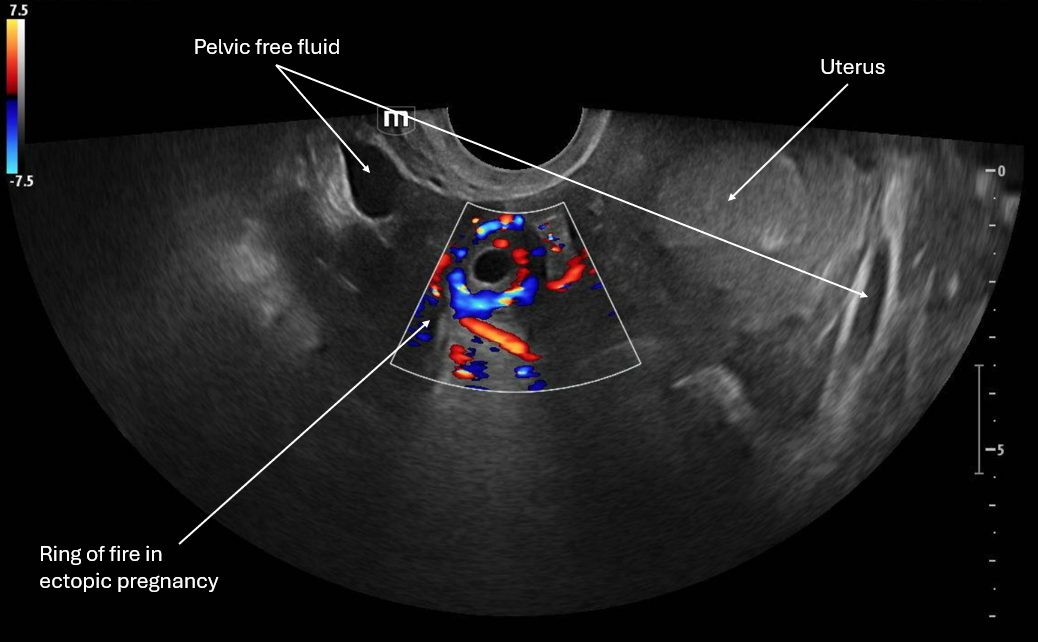

This image applies color flow to the suspected ectopic pregnancy and this shows the "ring of fire" sign which indicates an area of high blood flow due to increased vascularity to the ectopic pregnancy. This "ring of fire" can also be a normal finding with corpus luteum cysts so correlate with other ultrasound findings like free fluid in the pelvis and other elements of the clinical picture.

• Circumferential Doppler flow around adnexal mass = hypervascular tissue

• NOT diagnostic alone (corpus luteum can look identical)

• Think ectopic if: +hCG + empty uterus + adnexal mass

• Free fluid in the pelvis, RUQ +/- unstable vital signs is a ruptured ectopic until proven otherwise